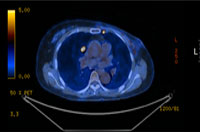

PET CT

유방암을 진단함에 있어서 최신의 미세침 흡인세포검사, 정위적 (Stereotactic) 조직검사 및 맘모튬 조직검사를 사용하고 있으며, 그로 인해서 진단의 정확도와 절제 성공률을 높이고 있습니다. 유방암을 확진하면 그다음으로는 병기를 결정하기 위해서 여러 가지 검사를 시행합니다. PET와 MRI, 전신 골스캔 검사, 폐, 복부 CT 스캔 검사 등의 다양한 검사를 통해서 전이 여부 및 환자의 수술 전 병기를 정확하게 확인합니다.